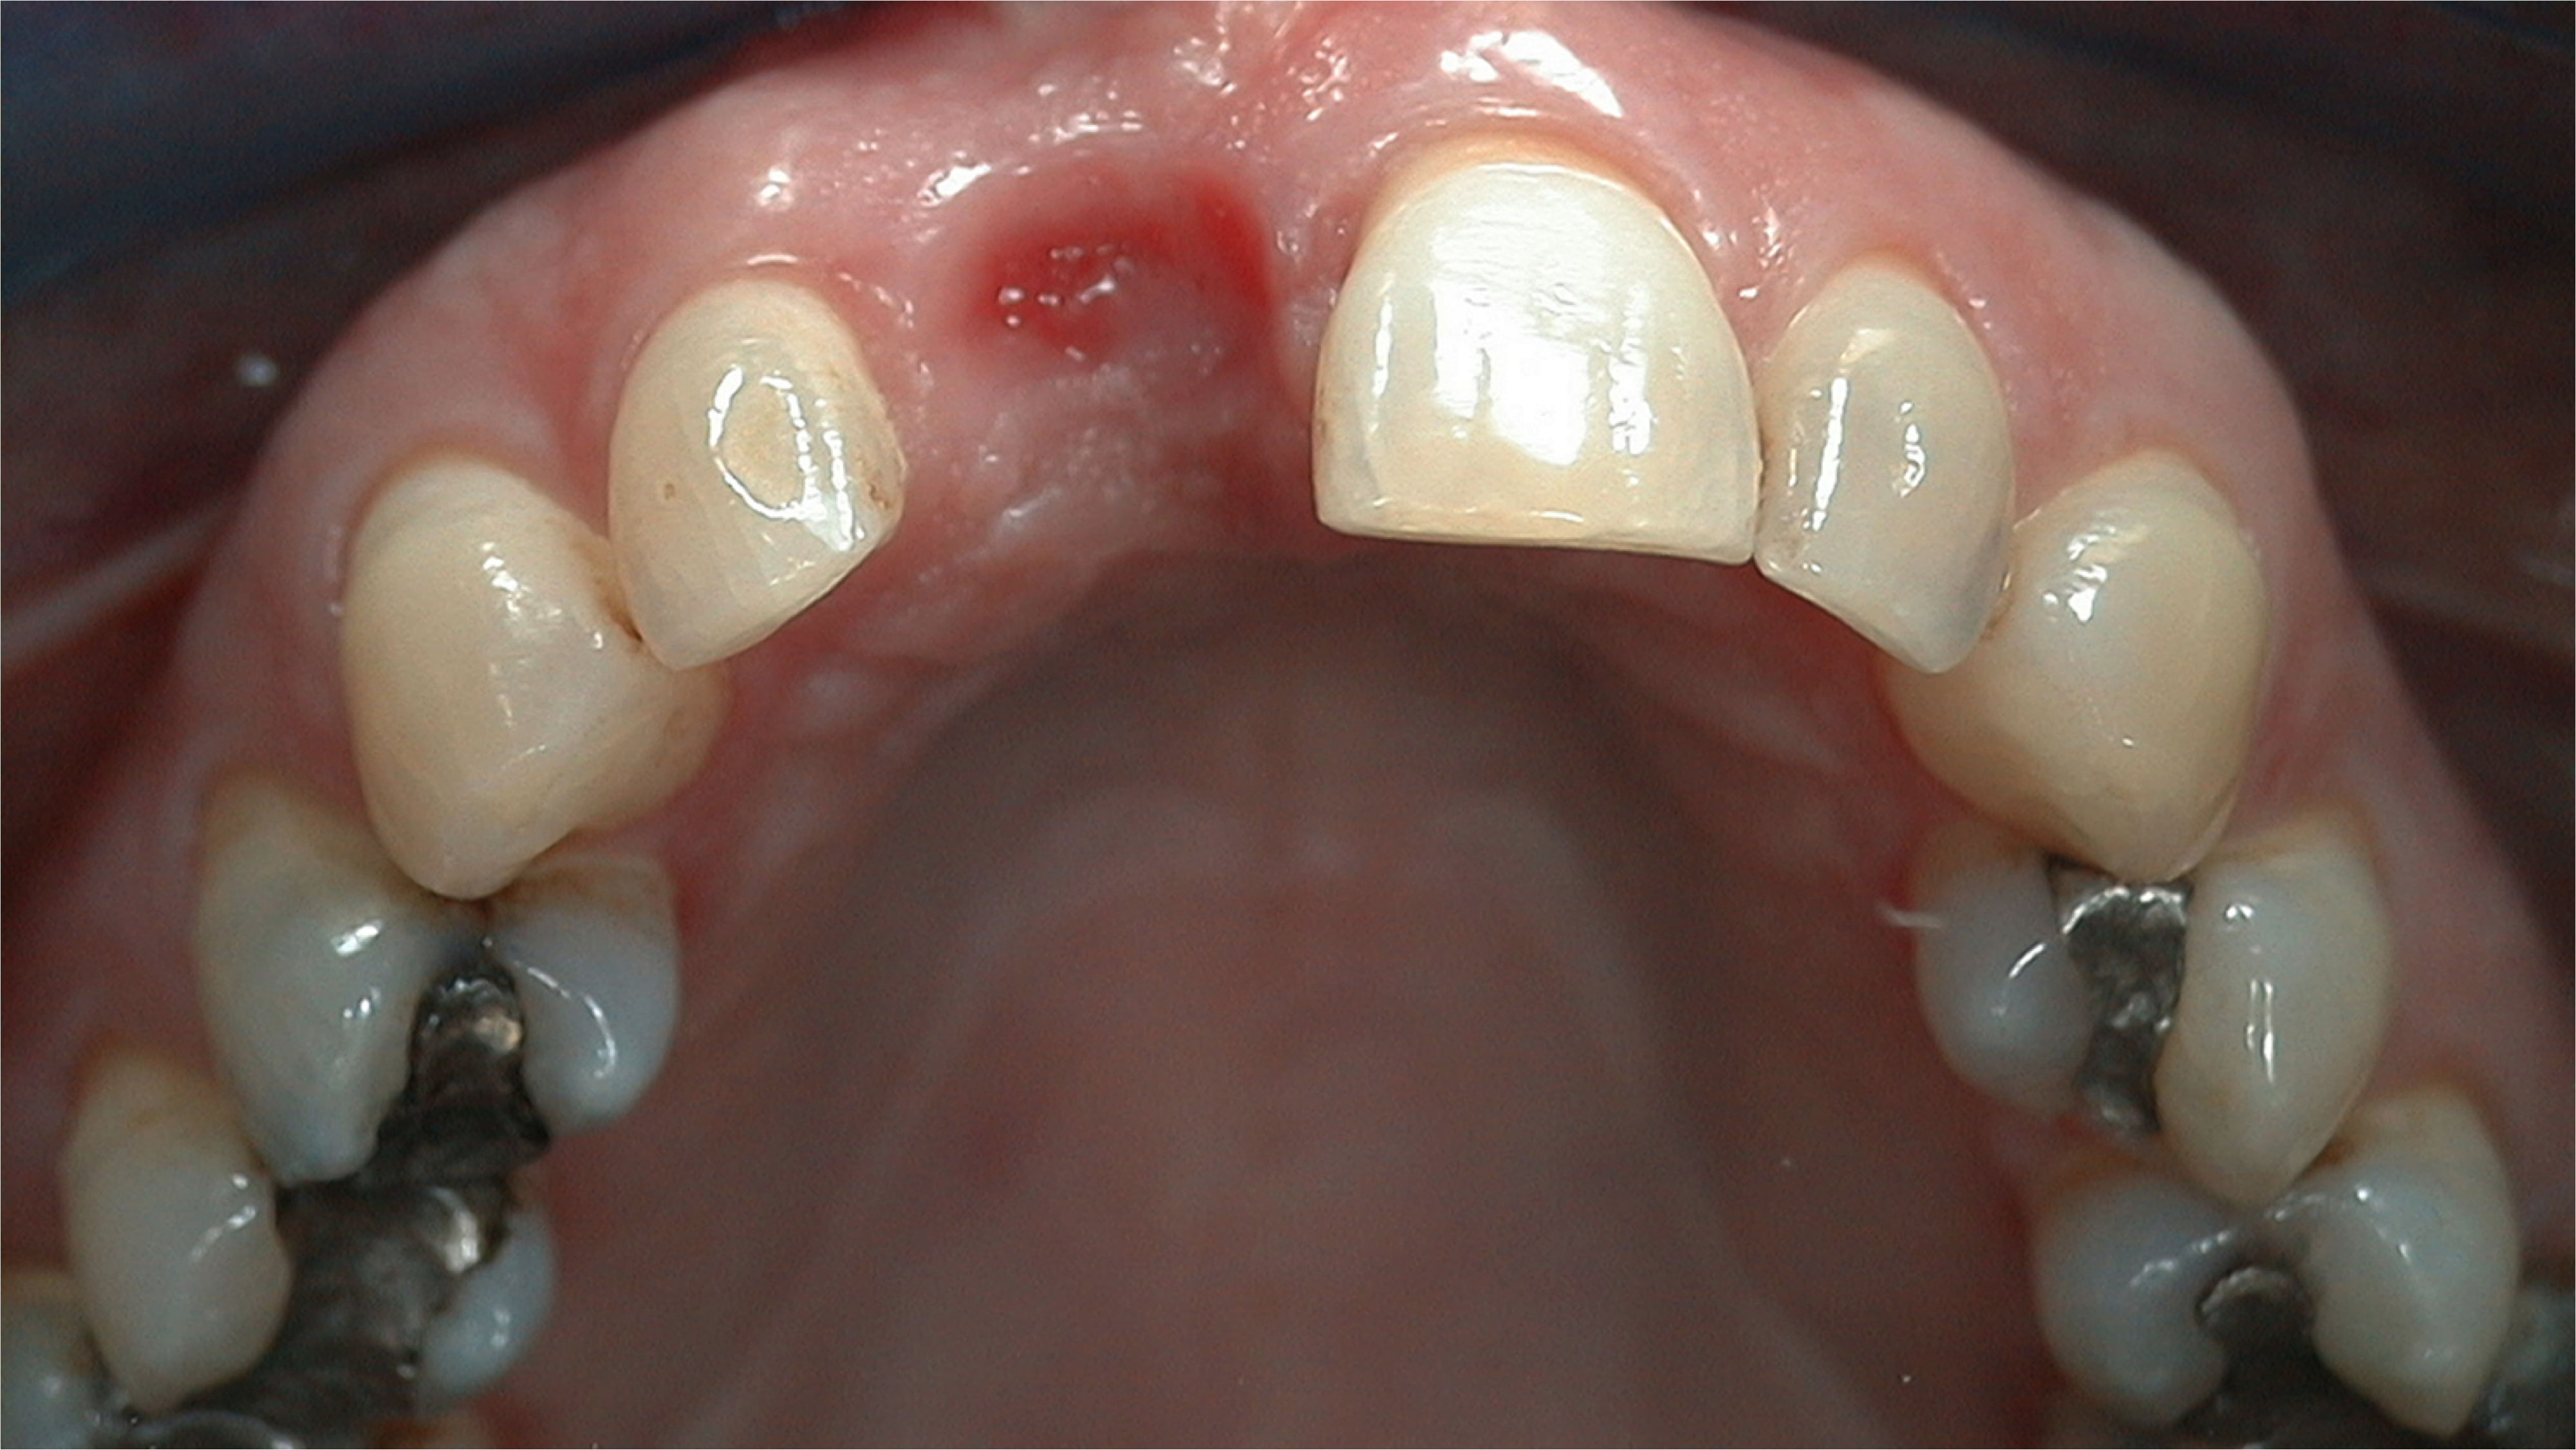

An example illustrating the manner in which these factors are considered in case selection, implant placement, and implant restoration is the case of a female patient who presented with a missing central incisor, tooth No. 8 (Figure 1 and Figure 2). While this example presents an ideal situation for a single implant-supported restoration, analysis is required to determine the appropriate implant width and length, presence of adequate bone, quality and quantity, soft-tissue health, abutment type (ie, custom or stock), and restoration type (ie, cement- or screw-retained).

Fig 2. The ridge was of adequate size and dimension, so a 4.3-mm implant was selected.

Figure 2

Radiographic examination of the site for implant placement is essential to determine the presence of adequate space for the implant and subsequent restoration (eg, central incisor) and to assess soft-tissue architecture.1,2 Computed tomography (CT) images and panoramic radiographs (eg, panorex) have been used in implant dentistry to help identify structures critical for implant placement and establish the safe, short distance for implant placement (ie, vertical control of implant placement) using a pilot drill (Figure 4).5

A flap procedure reveals the bone, which should be wide enough to provide 1.5 mm of bone on either side of the implant (Figure 5).6 The amount and level of bone surrounding implants is important for osseointegration, esthetics, and long-term survival.6 The location for implant placement can then be established using a round bur to place a mark in the center of the crest of bone from mesial-distally and facial-palatally (Figure 6).